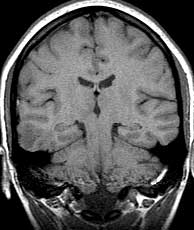

T1 coronals pre-gad

Findings: Focus of low signal in the cortex of the right middle and inferior temporal gyri (a). Cerebral aqueduct (aq) leading from the 3rd (3v) to the 4th (4v) ventricle. Crus of the fornix (crus). Flow enhancement in the sigmoid sinus (sig). Superior (stg), middle (mtg) and inferior (itg) temporal gyri. Hippocampus (hip). Body of the corpus callosum (body). Insula (in). Cerebellar tonsils (ton). Cingulate gyrus (cgy) and sulcus (csu). Body of the caudate nucleus (caud). Horizontal fissure (hor).